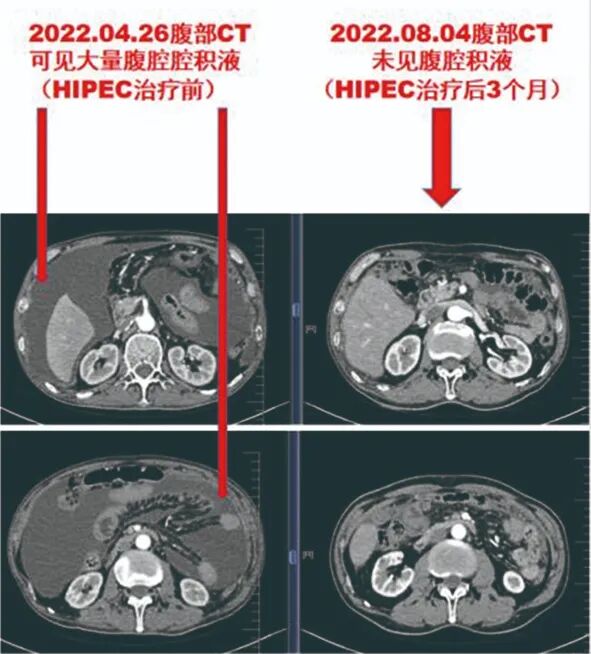

卢某,男,2021年9月因腹胀就诊,后确诊为恶性间皮瘤,2021年10月-2022年2月,患者于外院治疗,效果不理想,腹腔积液逐渐增多,患者生活不便,生活质量明显下降。

2022年4月,患者到肿瘤一科(放疗科)就诊,行顺铂腹腔热灌注化疗(HIPEC)+深部热疗。至2022年9月,患者随访4个月,腹腔积液治疗评效已达完全缓解,腹腔内基本无积液。同时发现,患者胸腔积液较治疗前明显吸收好转。